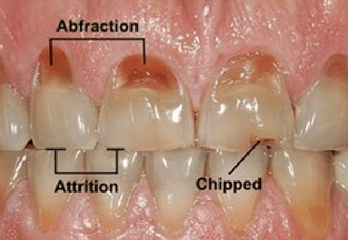

ABFRACTION lesions arises from clenching and is more common in the back (posterior) teeth and the canines but they can occur in the front (anterior) teeth as well. The characteristic appearance is of a straight line break parallel to the occlusal plane near the gumline and it causes the gums to recede. The straight line wedge breakage is a feature of the stress fracture of a hard tooth structure from the bending of the tooth when you gnash them together and move your jaw side to side. Studies have shown that when you do this in your sleep it can be up to 40 times stronger than you could do it when you are awake. You could not do it even if you tried when you are conscious as your higher brain will stop you from doing so. Bruxism is proportional to stress.

When the enamel has broken the dentine ( soft part of the tooth underneath the enamel) can erodes giving these lesion the appearance of acid erosion and toothbrush abrasion. You can of course get decay in these areas once broken as it can become a food trap. While it is possible to have the acid erosion, I do not believe toothbrush abrasion is a likely culprit. These are secondary to the main issue of the abfraction which is in fact the result of bruxism.